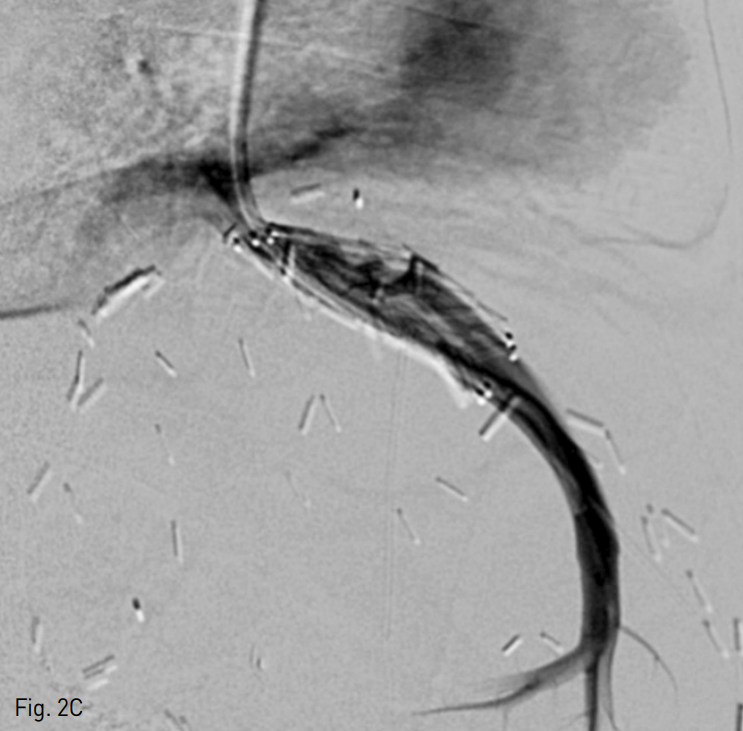

복부 초음파 검사에서 간정맥의 중심 부위에 에코성의 충만결손 병변이 관찰되며 이는 혈전으로 생각되었다. 도플러 검사 상 간 정맥 내의 혈류 신호가 감지되지 않았다 (Fig. 1).

Fig. 1

A Doppler ultrasonography of an 11-month-old male patient revealed no flow signal within the hepatic vein. Note the echogenic filling defect in the central portion of the hepatic vein near the anastomosis site, which is presumed to be a thrombus (arrow).